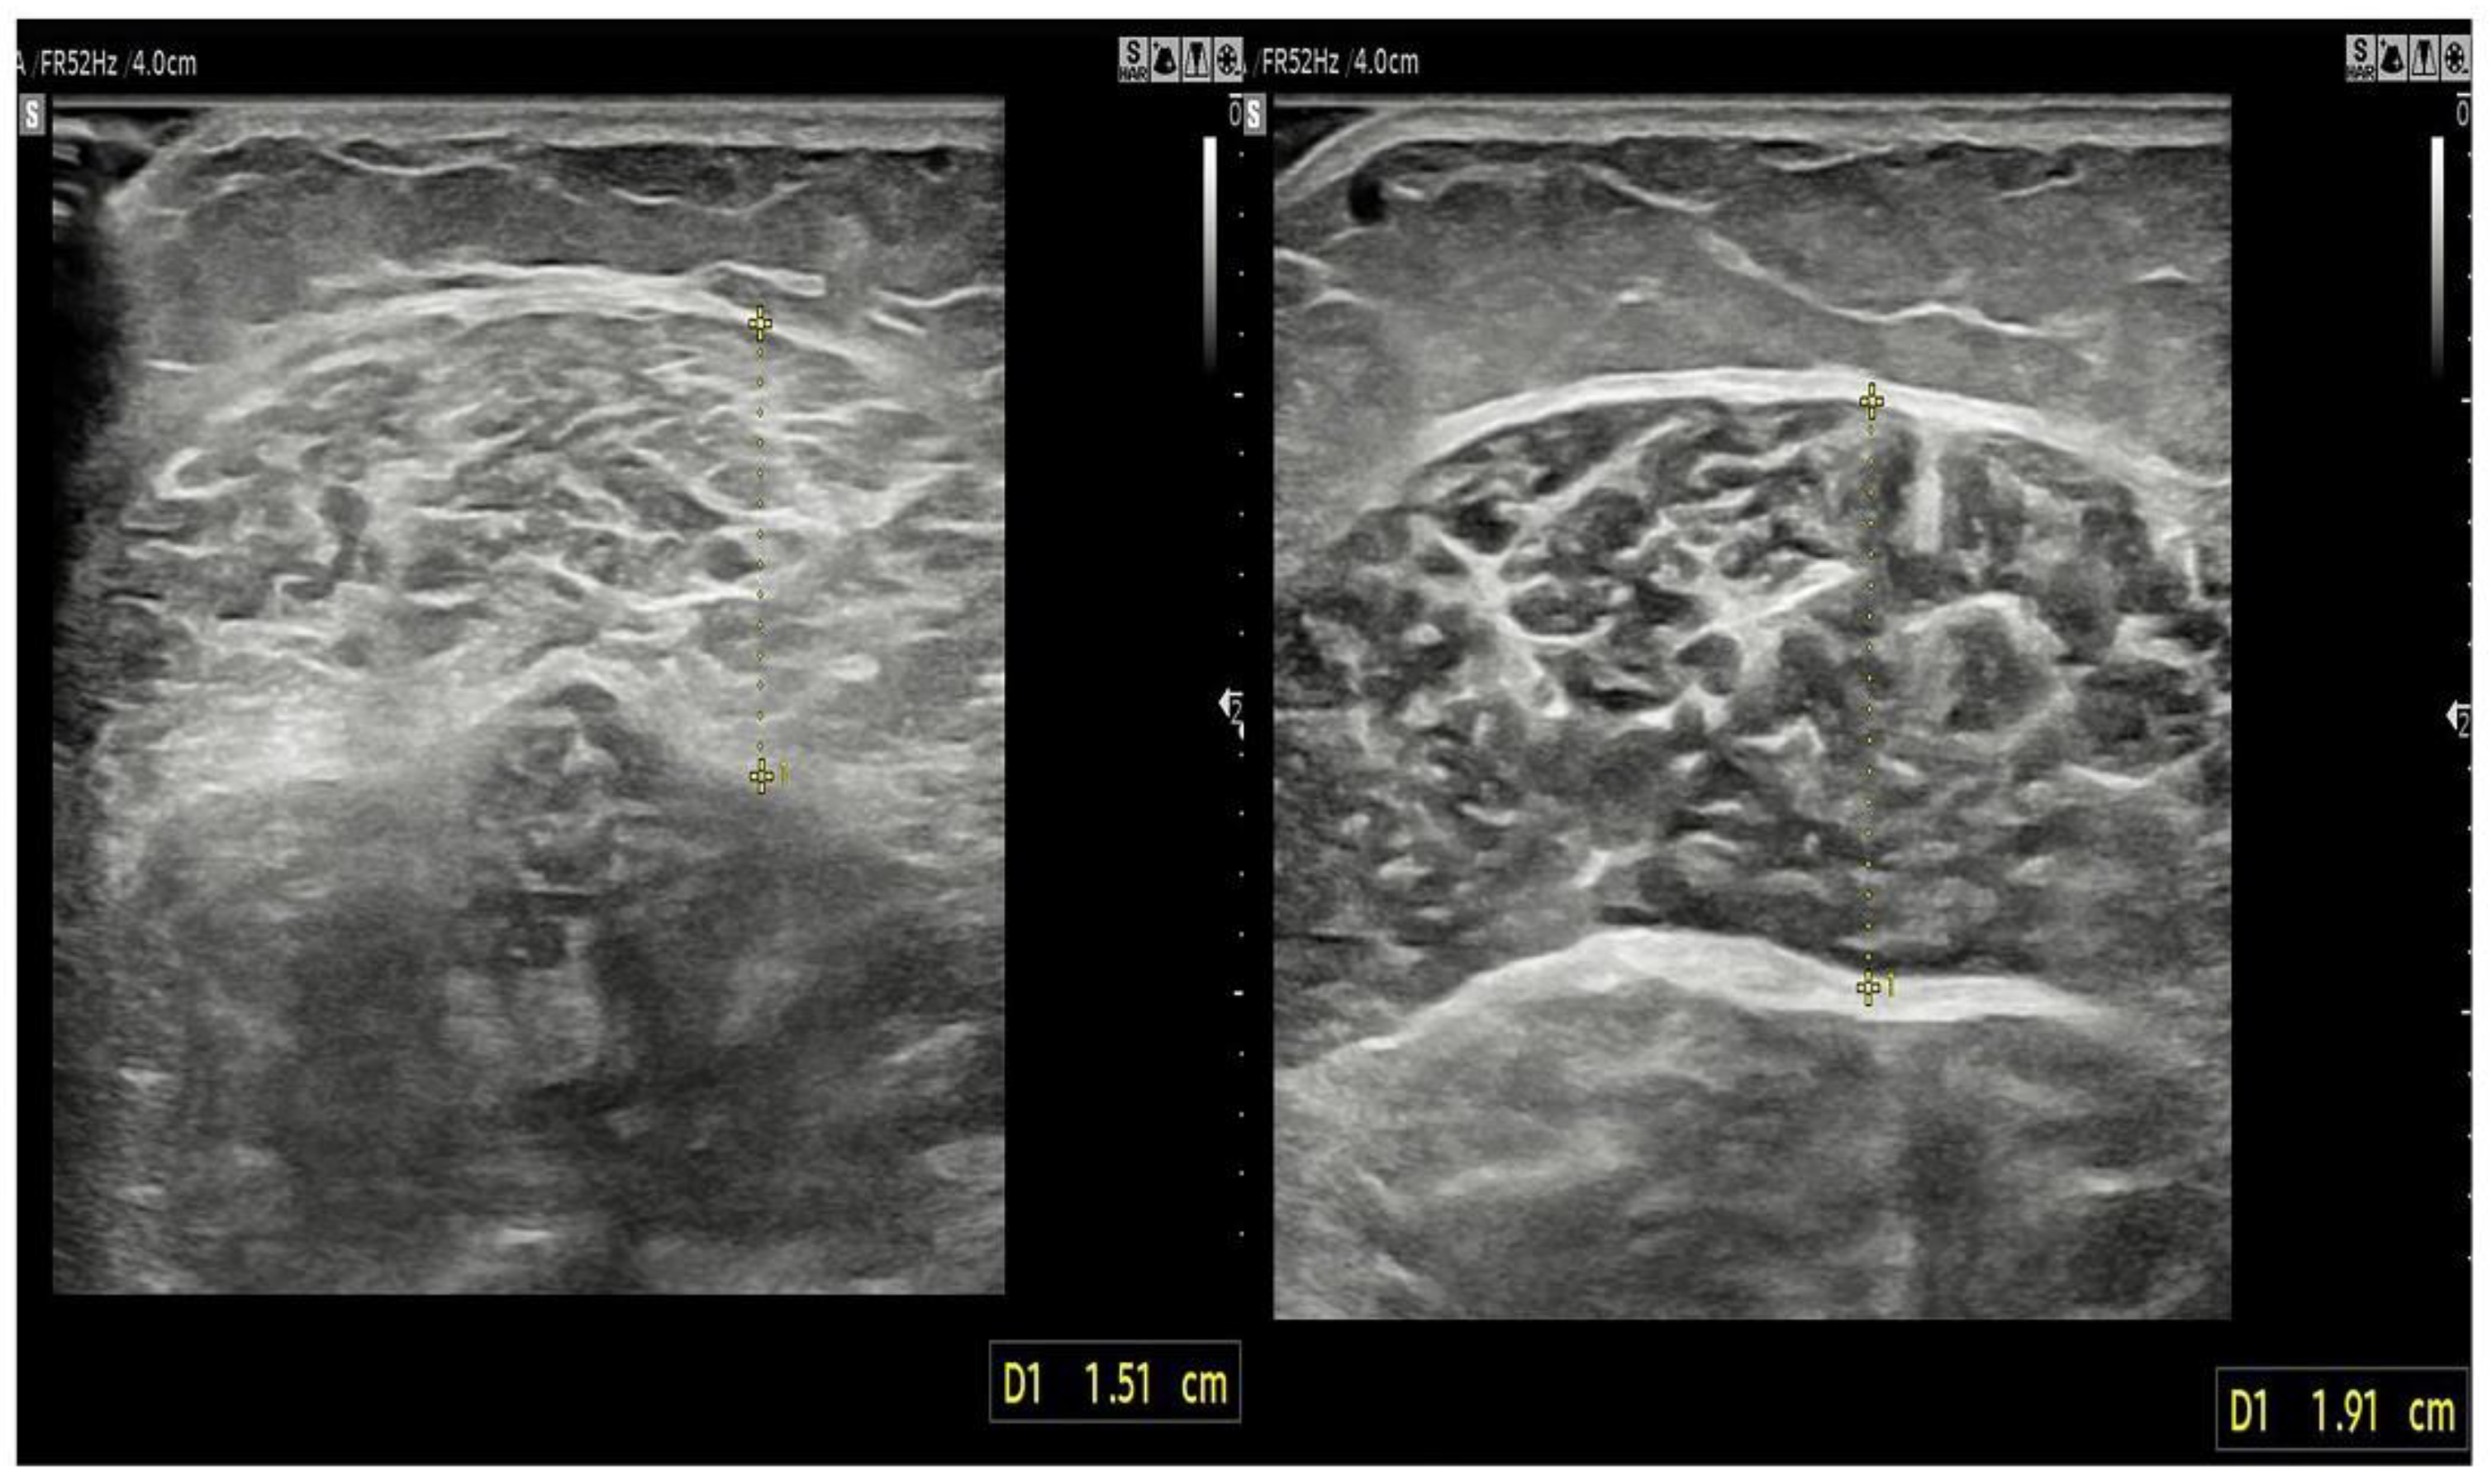

2.3.4. Stiffness and Thickness of the Muscle

| Muscle thickness and stiffness | ||||

| Tibialis anterior | ||||

| thickness (mm) | 23.72 ± 0.36 | 24.97 ± 0.33 | 0.062 | 0.125 (0.257~0.006) |

| Gastrocnemius medial head | ||||

| thickness (mm) | 17.65 ± 0.27 | 19.05 ± 0.28 | 0.008 | 0.145 (0.037~0.253) |